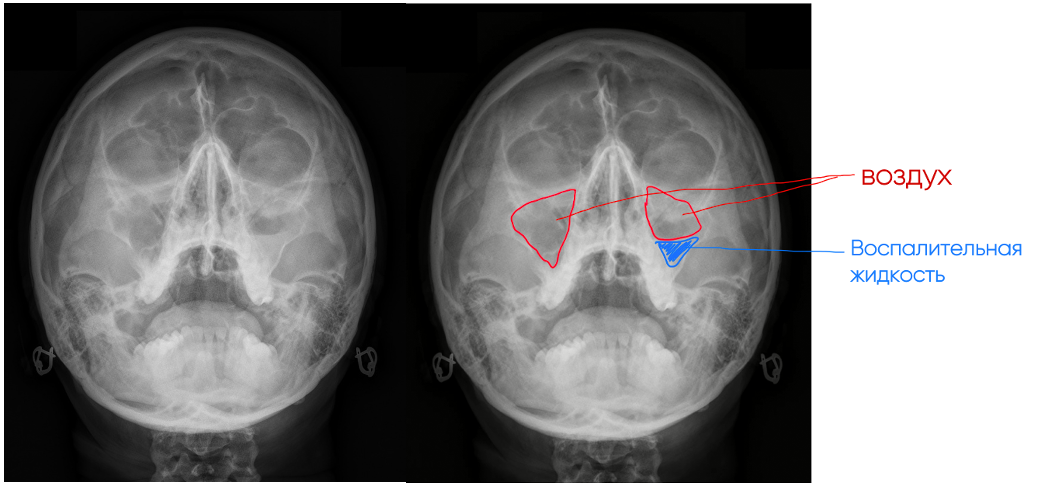

На этом снимке ситуация кажется еще более очевидной.

Опять же в первую очередь смотрим на гайморовы пазухи, рисуем их контур и понимаем, что воздушная часть пазух достаточна мелкая. Остальная же часть их заполнена воспалительной жидкостью, и разница межу ним и воздухом тут достаточно очевидная (красное-воздух, синее – воспалительный компонент). Это двусторонний гайморит.

Также обращаем внимание на лобные пазухи (обозначены желтым), воздушность которых снижена. Вероятно, здесь тоже имеется воспаление.